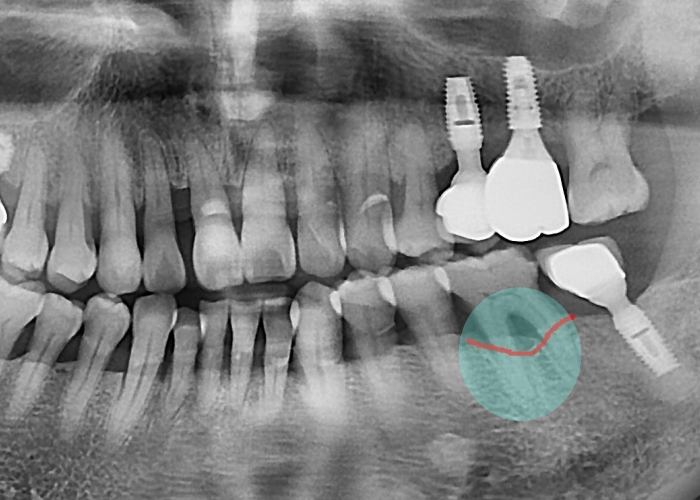

2년 정도가 경과하게 되면

방사선 사진에서

뿌리 주변의 뼈가 점차 줄어들고,

뿌리 일부가 드러나기 시작합니다.

이 시점은 과잉진료가 아니라

오히려 적절한 임플란트 시기(골든타임)입니다.

뼈가 아직 충분히 남아 있어

수술이 단순하고,

수복 후의 결과도 안정적입니다.